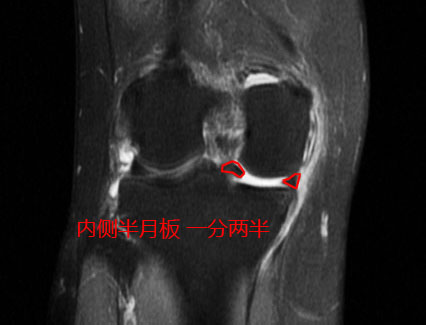

针对小萱阿姨这样的情况,谢医生给她进行了详细的查体,并没有明显的变形,关节屈伸的角度也没有明显的异常,但是她内侧关节间隙有明显的压痛,半月板的相关查体非常的典型,结合她当年的核磁结果,可以判断她的内侧半月板发生了明显的撕裂,而且是一种比较重的撕裂,叫做桶柄状撕裂。

简单地解释这个桶柄状撕裂,大家可以想象成一个饼,我们把它从中间撕开两半,靠近关节腔内的这一半撕裂的半月板,就会经常在运动的过程当中造成关节的卡顿,所以小萱阿姨才会经常的出现关节的绞索。

由于已经过去了4年没有再复查核磁,谢医生给她安排了核磁检查,在复查的过程当中我们可以看到非常好的一点是,经历了4年,她的关节软骨还真就没有被破裂的的半月板明显的磨损掉,但是桶柄状的撕裂,没有任何愈合的迹象,在核磁上我们仍然可以看到非常经典的双后交叉韧带征,这说明仍然有大部分的半月板撕裂后,卡在了关节腔内。